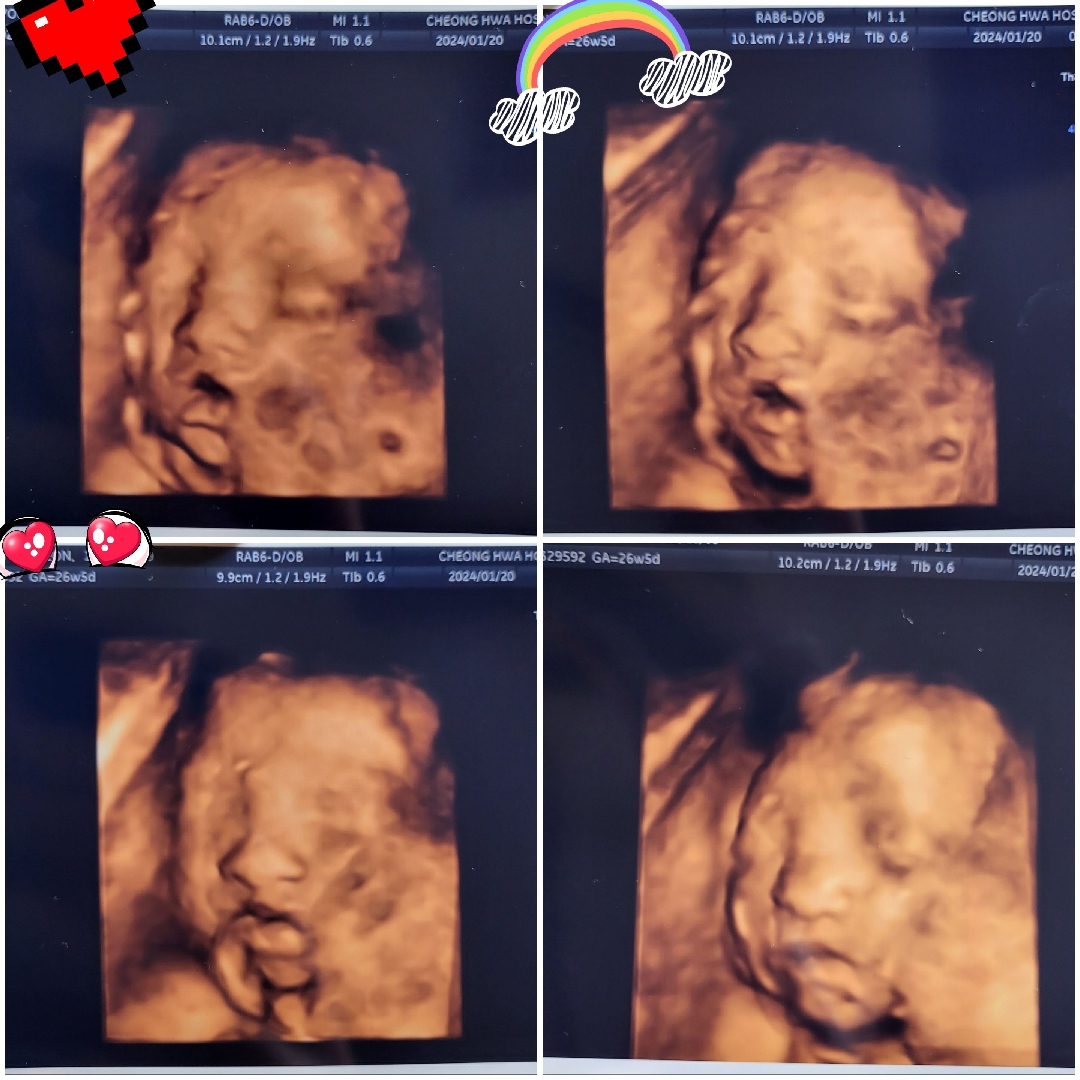

26주 5일에 찍은 딸내미 입체 초음파 사진입니다~ 이렇게 얼굴을 보니 정말 실감이 나는것같아요~^^ 모두 힘내세요~